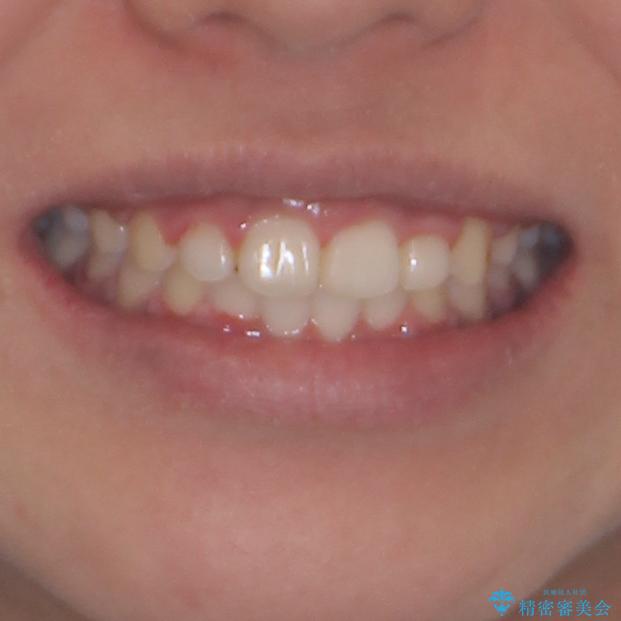

- 上下前歯の叢生を気にして来院された患者様です。

当初はインビザラインにて治療を開始しましたが、自己管理による治療が難しくなり、ワイヤー矯正へ転換して継続しました。

2年ほどインビザライン矯正を続けましたが、終了することができず、ワイヤーへ転換後は1年弱で終えることができました。